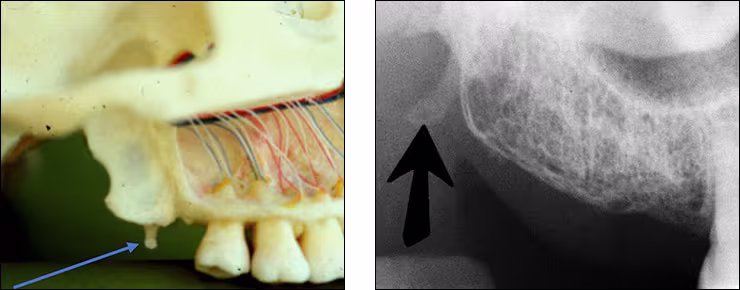

Maxillary sinus – The maxillary sinus is one of the paired paranasal sinuses. This prominent radiolucent air-filled cavity is located above the posterior teeth on the right and left sides of the maxilla. The sinus cavities are horizontally oblong bilateral structures with fine radiopaque borders. The maxillary sinus may contain septa which appear as radiopaque lines within the body of the sinus cavity. The size of the maxillary sinus can be quite variable and sometimes encroaches into the alveolar process, especially when posterior teeth are missing. Typically, the sinus appears uniform right to left. The maxillary sinus is sometimes referred to as the maxillary antrum and can be observed on both maxillary premolar and molar periapical images and partially on lateral-canine periapical images.

Zygomatic bone – The zygomatic bone or cheek bone attaches to the right and left sides of the posterior maxilla. The zygomatic bone, quadrangular in shape, broadens as it extends posteriorly. This bilateral radiopaque structure is also known as the malar bone. The zygomatic bone can be seen on maxillary premolar and molar periapical images.

Zygomatic process - The zygomatic process is the radiopaque U-shaped structure representing where the zygomatic bone attaches to the maxilla. The zygomatic process of the maxilla is the most anterior aspect of the zygomatic bone. The process is positioned toward the midline while the bone extends posteriorly away from the midline. This structure is sometimes referred to as the malar process and can be seen on maxillary premolar and molar periapical images.

Coronoid process – The coronoid process of the mandible is the triangular bony portion of the anterosuperior aspect of the ramus. This mandibular structure can be recorded on maxillary molar periapical images as the ramus moves forward when the patient’s mouth is open. It appears as a bilateral triangular or thumb-like radiopacity on posterior maxillary images. The triangular portion projects forward toward the midline. The coronoid process is the only mandibular structure recorded on maxillary molar periapical images.

Maxillary tuberosity – The maxillary tuberosity is the rounded end of the alveolar process of the maxilla. This radiopaque structure appears bilaterally on maxillary molar periapical images and often on maxillary premolar periapical images and molar bitewings. The tuberosity curves upward at the end of the maxillary alveolar process. The tuberosity gives a smile appearance to the maxilla and the dentition particularly on bitewings.

Pterygoid plates – The lateral and medial pterygoid plates are located behind the maxillary tuberosity. They project a single image configured like a thin wing of bone extending posteriorly from the tuberosity. This bilateral radiopacity is occasionally recorded on maxillary molar periapical images when the receptor is positioned adequately posterior.

Hamular process – The hamular process or pterygoid hamulus is a tiny finger or hook-like projection of bone that extends inferiorly from the medial pterygoid plate. This bilateral radiopacity occasionally appears on maxillary molar periapical images and molar bitewings when the receptor is positioned sufficiently posterior to record it.